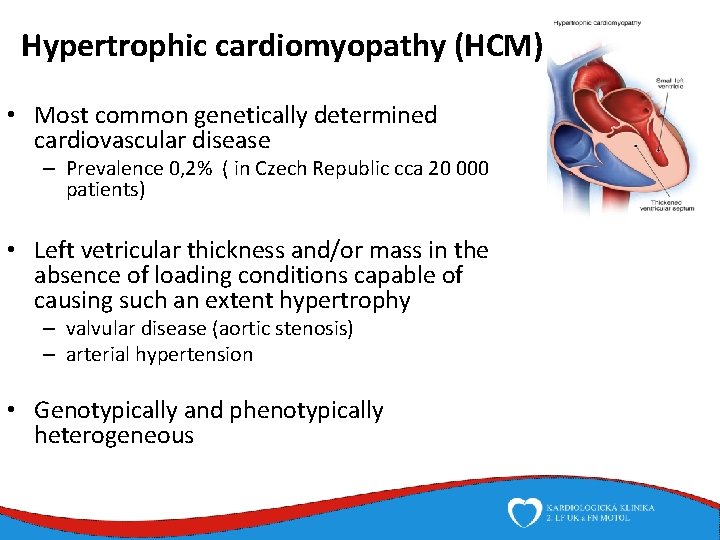

Hypertrophic cardiomyopathy (HCM) • Most common genetically determined cardiovascular disease – Prevalence 0, 2% ( in Czech Republic cca 20 000 patients) • Left vetricular thickness and/or mass in the absence of loading conditions capable of causing such an extent hypertrophy – valvular disease (aortic stenosis) – arterial hypertension • Genotypically and phenotypically heterogeneous